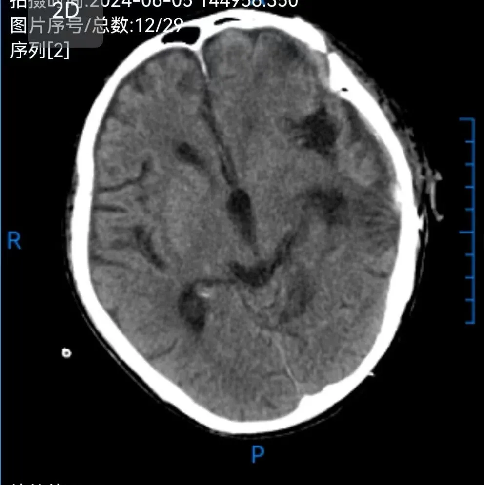

患者汪某,男性,66歲,因重症顱腦(nǎo)損傷,多發肋骨(gǔ)骨折,血氣胸,鎖骨骨折辦理入院緊急手術,醫院神經外科專家團隊為患者行開顱血腫清除+大骨瓣減壓術。手術順利,術後(hòu)恢複滿意。專家團隊將患者手術去除的顱骨骨瓣進行了清洗、滅菌後低(dī)溫冰凍儲存。

患者術後滿三個月(yuè)再次返院進(jìn)行顱骨缺損(sǔn)修補術,經過完善術前檢查、全(quán)科討論、做好充分手術(shù)準備後,武(wǔ)寧縣總醫院人民醫院院區神(shén)經外科團隊成功為患者完成(chéng)自體顱骨修補術(shù)。

術前: